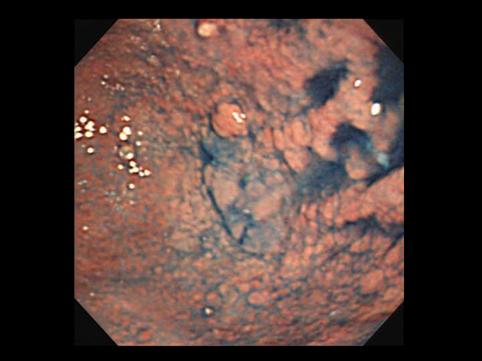

疾病(病理主体)的分类恶性上皮性肿瘤/腺癌

部位(按器官分)胃(部位)/2个以上

检查方法内窥镜

肿瘤的肉眼分类0型(表在型)/IIb型(IIb+IIa)

肿瘤最大直径40以上

肿瘤的深度m